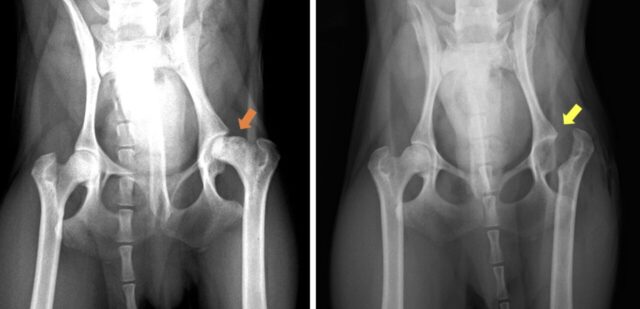

左写真:正常な大腿骨頭、右写真:大腿骨頭壊死症によって軟骨びらん(黄色矢印)と変形を認める。

術前のレントゲン写真(左):壊死した大腿骨頭(オレンジ矢印)

術後のレントゲン写真(右):大腿骨頭を摘出している(黄色矢印)

疼痛を緩和する目的で大腿骨頭切除(FHO)を実施しました。摘出した大腿骨頭は広範囲に軟骨びらんが認められ、強い変形を認めました。本手術後は股関節がなくなるため、手術をした足のバランスが取りづらくなります。そのため、術後はリハビリが重要になります。ケンちゃんの場合、週に1回のリハビリを2ヶ月間通院していただきました。術後2ヶ月では正常な歩行に改善し、臀部や大腿部の筋肉量も回復しました。